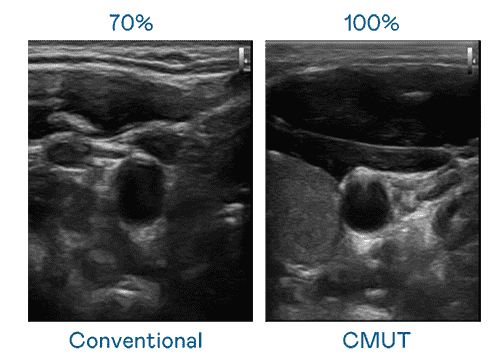

CMUT 技术是一种用电容式微机电元件来产生超音波讯号的技术。。。。与传统 PZT 压电式技术相比,,,CMUT 频宽增加 30%,,,,更宽频的超音波讯号让影像解析度大幅提升,,,,是实现高影像品质医疗超音波扫描、、促进精准医疗发展的关键技术。。

大频宽带来超清晰影像

超音波影像的解析度高低,,,,首先取决于探头能发出的讯号频宽。。。。蓝狮在线 CMUT 可提供高清晰的超音波讯号,,提供高频宽、、、、高灵敏度、、影像纹理细节更高的超音波影像,,,协助医护人员缩短影像判读时间及利用精准的医疗影像进行诊断。。。。